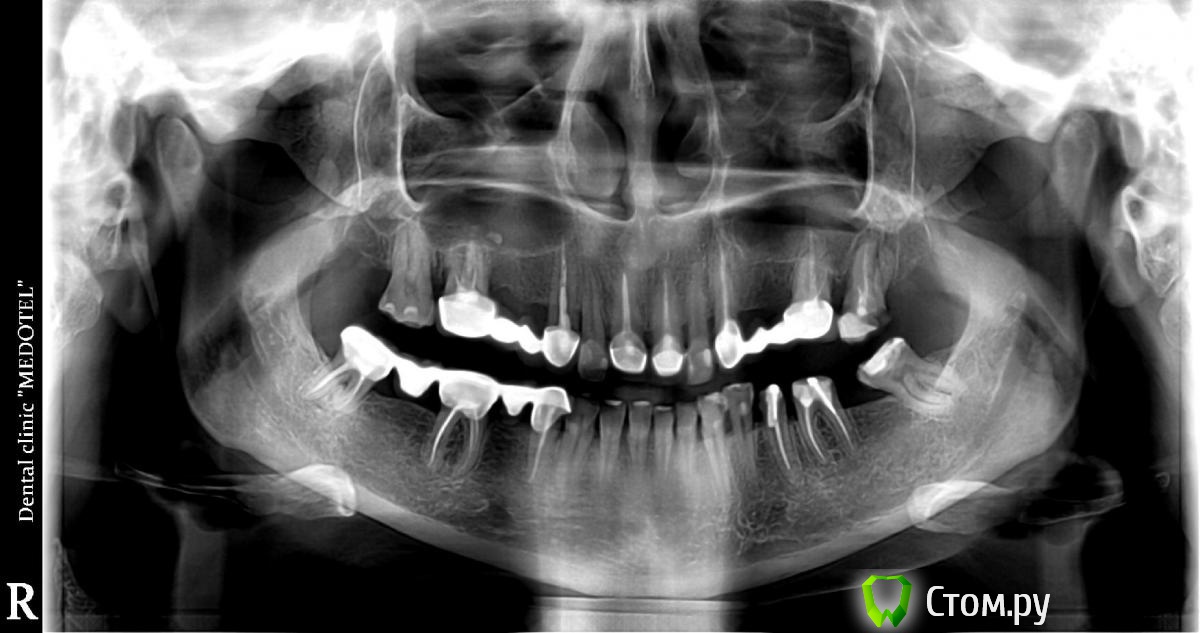

Панорамный снимок прилагается.  Заранее спасибо.

Вижу тут несколько удалений несколько имплантаций и пару костных пластик :-)